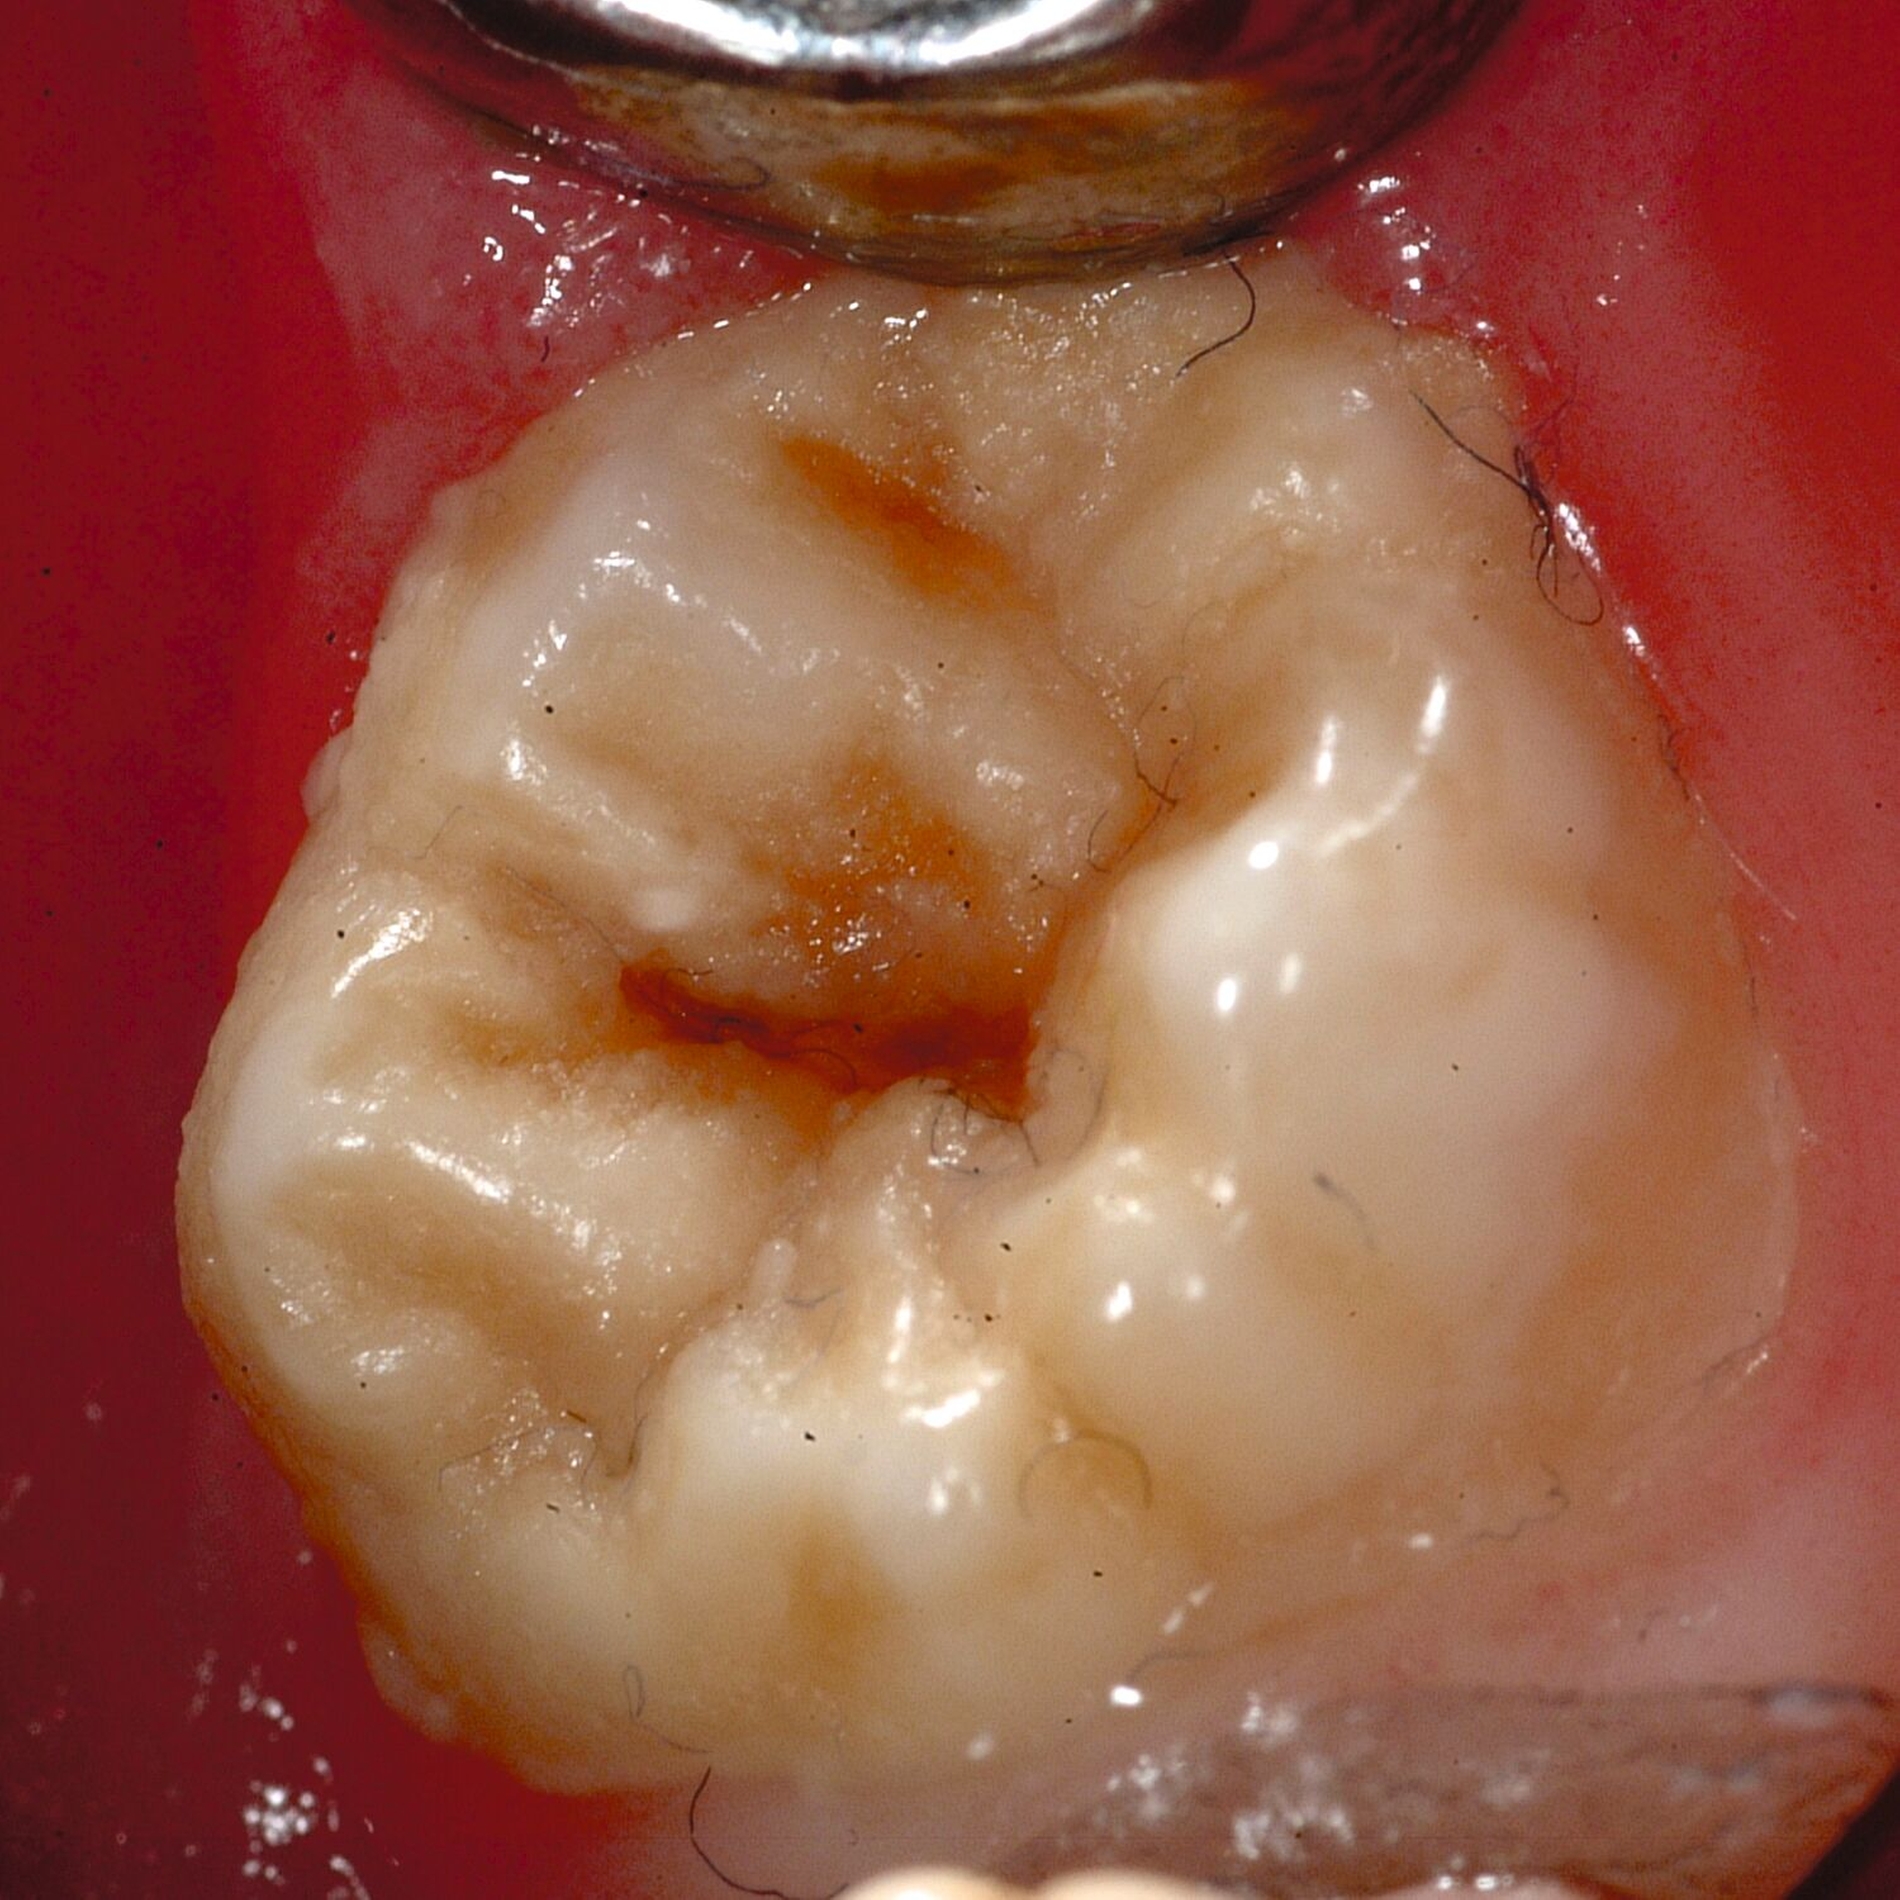

An umfangreich hypomineralisierten Zähnen können Schmelzeinbrüche (engl.: „enamel breakdown“ oder „enamel desintegration“, Abbildung 5) auftreten [Lygidakis et al., 2010; 2022]. Da diese oftmals die Folge einer fehlenden Belastungsfähigkeit des Zahnschmelzes sind und erst nach der Einstellung der Zähne in die Okklusion auftreten, werden sie auch als posteruptive Schmelzeinbrüche bezeichnet. Sie sind häufig im Bereich der Kauflächen beziehungsweise Höcker der Molaren zu finden, führen zur Dentinexposition und damit einhergehend zu ausgeprägten Hypersensitiven insbesondere bei Kindern, deren Zähne gerade erst durchgebrochen sind [Linner et al., 2021].

Frontzähne sind seltener von MIH-bedingten Schmelzeinbrüchen und Hypersensitivitäten betroffen. Von den posteruptiven Oberflächeneinbrüchen sind präeruptive Defekte abzugrenzen. Diese Zähne brechen bereits mit einem vorhandenen Oberflächendefekt in die Mundhöhle durch.

Für die Dokumentation und Klassifikation der MIH wurden verschiedene Systeme vorgeschlagen. Als historisch und veraltet gilt der (modifizierte) DDE-Index. Demgegenüber haben die Kriterien der EAPD – abgegrenzte Opazitäten (Abbildung 3 und 4), Schmelzeinbrüche (Abbildung 5), atypische Restaurationen (Abbildung 6) – mittlerweile die weiteste Verbreitung gefunden. Diese wurden 2003 erstmals zur Beschreibung der MIH auf empirischer Basis publiziert [Weerheijm et al., 2003] und den Jahren 2010 und 2022 im Rahmen der damaligen MIH-Workshops bestätigt [Lygidakis et al., 2010; 2022].